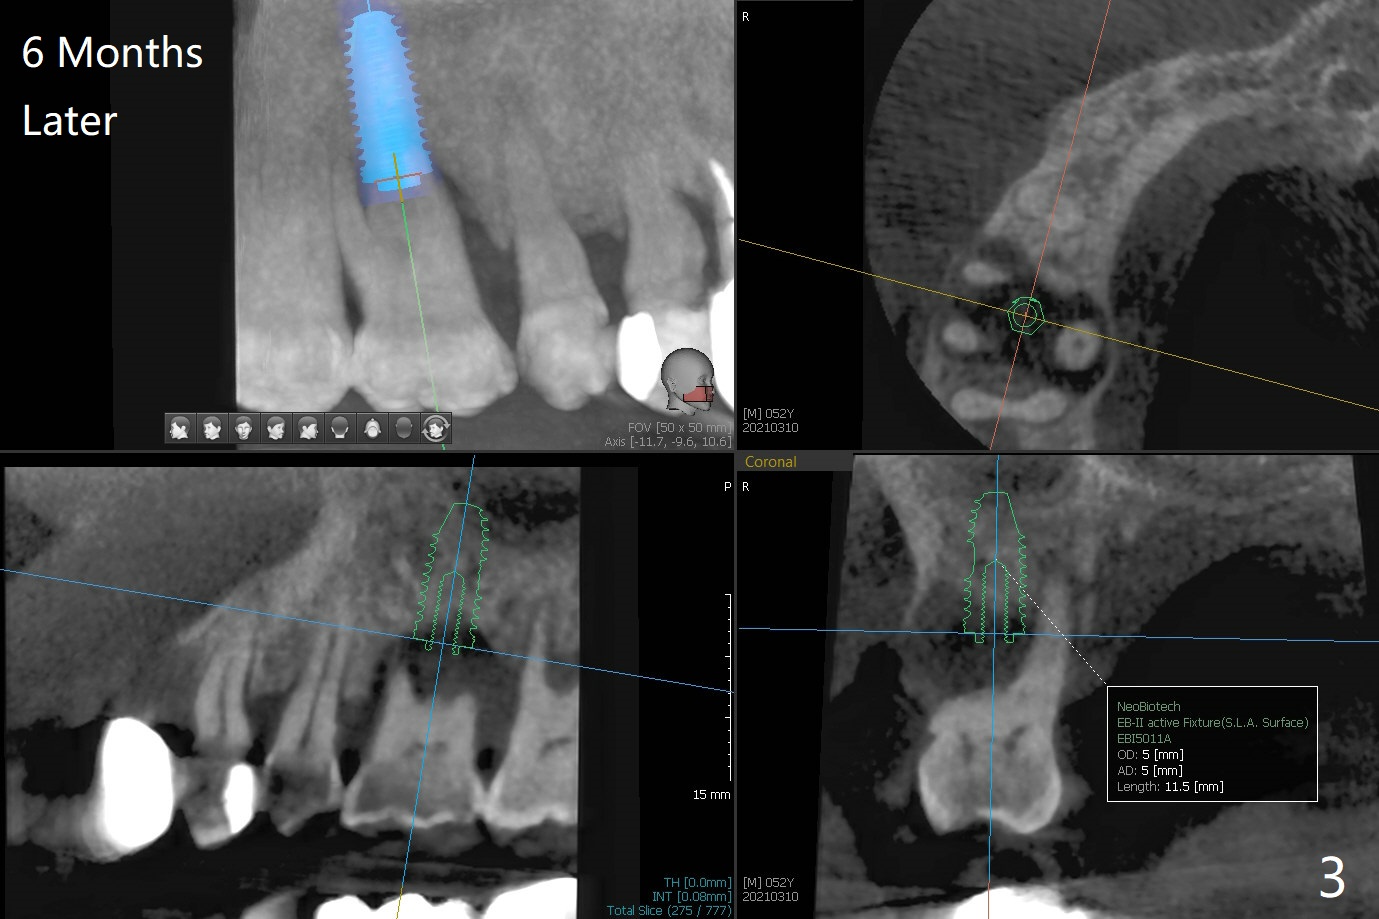

One month post cementation of the crown of #30, the opposing tooth (#3 in Fig.1) becomes symptomatic as related to the buccal furca (*). After periodontal maintenance, Arestin is placed at the furca. If the treatment does not achieve pain relief, the tooth will be removed with immediate implant free hand. Following 1.6 mm drill in the septum (Fig.2), insert its own parallel pin for PA (trajectory). After use of Marking Drill, use 4.3 mm Magic Drill with 9 mm stopper, followed by sticky bone and 4.5x10 IS dummy implant (crest level) for sinus lift (2nd PA). With confirmation of lift, insert the 1st piece of PRF membrane (small), more sticky bone and dummy. The definitive fixture will be 5x10 or 11 mm. Pack more sticky bone around the implant, especially buccal. Insert collagen dressing in the apical portion of the palatal socket if necessary. A temporary abutment (non-hex) should be easily placed. Insert 2nd piece of PRF membrane around the immediate provisional for complete seal. If it is still insecure, place periodontal dressing. In fact, the tooth is mobile with more severe bone loss 6 months later (Fig.3). Impression is taken for guide. 53 years old Male